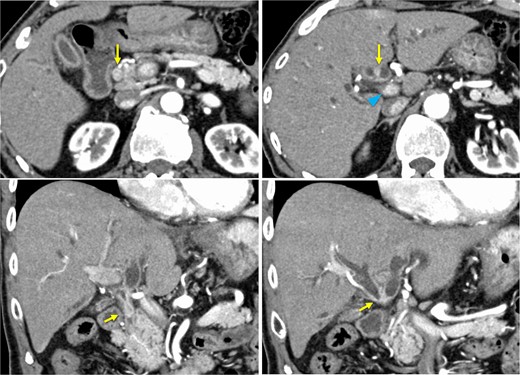

Bone marrow biopsy revealed a normal myeloid/erythroblast ratio and a slightly increased number of megakaryocytes without platelet adhesion (Fig. 2), consistent with ITP. The possibility of ITP secondary to pCCA was considered. Prednisolone therapy was initiated at 25 mg/day (0.5 mg/kg/day), with gradual dose reduction based on platelet response (Fig. 3). Lansoprazole 15 mg medication was also initiated for steroid ulcer prophylaxis.

Time course, as well as trends of platelet counts and prednisolone dose. PLT, platelet count; ERCP, endoscopic retrograde cholangiopancreatography; EBS, endoscopic retrograde stent.

Endoscopic retrograde cholangiopancreatography (ERCP) was subsequently performed after the platelet count exceeded 50 × 109 /L (perioperative Day 27), and an endoscopic biliary stent (EBS) was inserted. Cholangiography with magnetic resonance imaging and ERCP revealed full circumferential stenosis in the mid-to-upper bile ducts without left and right bile duct disconnections (Fig. 4). Intraductal ultrasonography further demonstrated superficial tumor involvement of the perihilar bile duct, without extension to the left or right hepatic ducts. Histological examination confirmed adenocarcinoma, consistent with Bismuth type II pCCA [8]. Tumor resection was planned when the Prednisolone dose was reduced to 5 mg/day, and the platelet count remained >100 × 109 /L.

On perioperative Day 78, the patient developed acute obstructive suppurative cholangitis, leading to a decrease in platelet count. Antibiotics (cefoperazone /sulbactam) and EBS replacement were effective in addressing this infection. Left hepatopancreatoduodenectomy with portal vein reconstruction was performed on perioperative Day 98. The bile duct and the portal vein were partially adherent, and the portion of portal vein was resected and reconstructed. The operative time was 399 min, and blood loss was 1300 ml, requiring two red blood cell units and 10 fresh frozen plasma units. Pathological examination confirmed well-differentiated tubular adenocarcinoma of the bile duct, flat-infiltrating type, T2aN1M0, Stage IIIC (UICC 8th edition [9]), with R0 resection (Fig. 5). Prednisolone therapy was discontinued postoperatively without ITP relapse. The patient was discharged on postoperative Day 22.